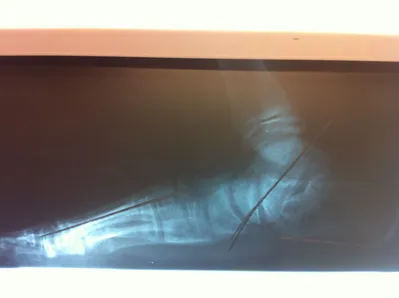

Below are x-rays of a foot pre-operatively (left) where the black line indicates and plantarflexed (downward directed) talus bone and post-surgical repair with a subtalar joint implant and lenthening of the calf muscle which allows the calcaneus (heel bone) to set underneath the talus and the implant keeps the talus from subluxing off the calcaneus and now the talus is more inline with the front of the foot (right).